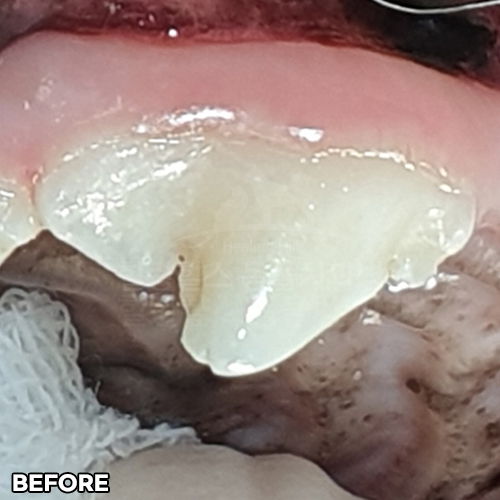

[강아지 잇몸에 고름] 최소침습적 발치 후 씨티로 확인된 자기잇몸뼈 증식! 치조골 살리는 힐링힐스 동물치과병원

2025.10.27